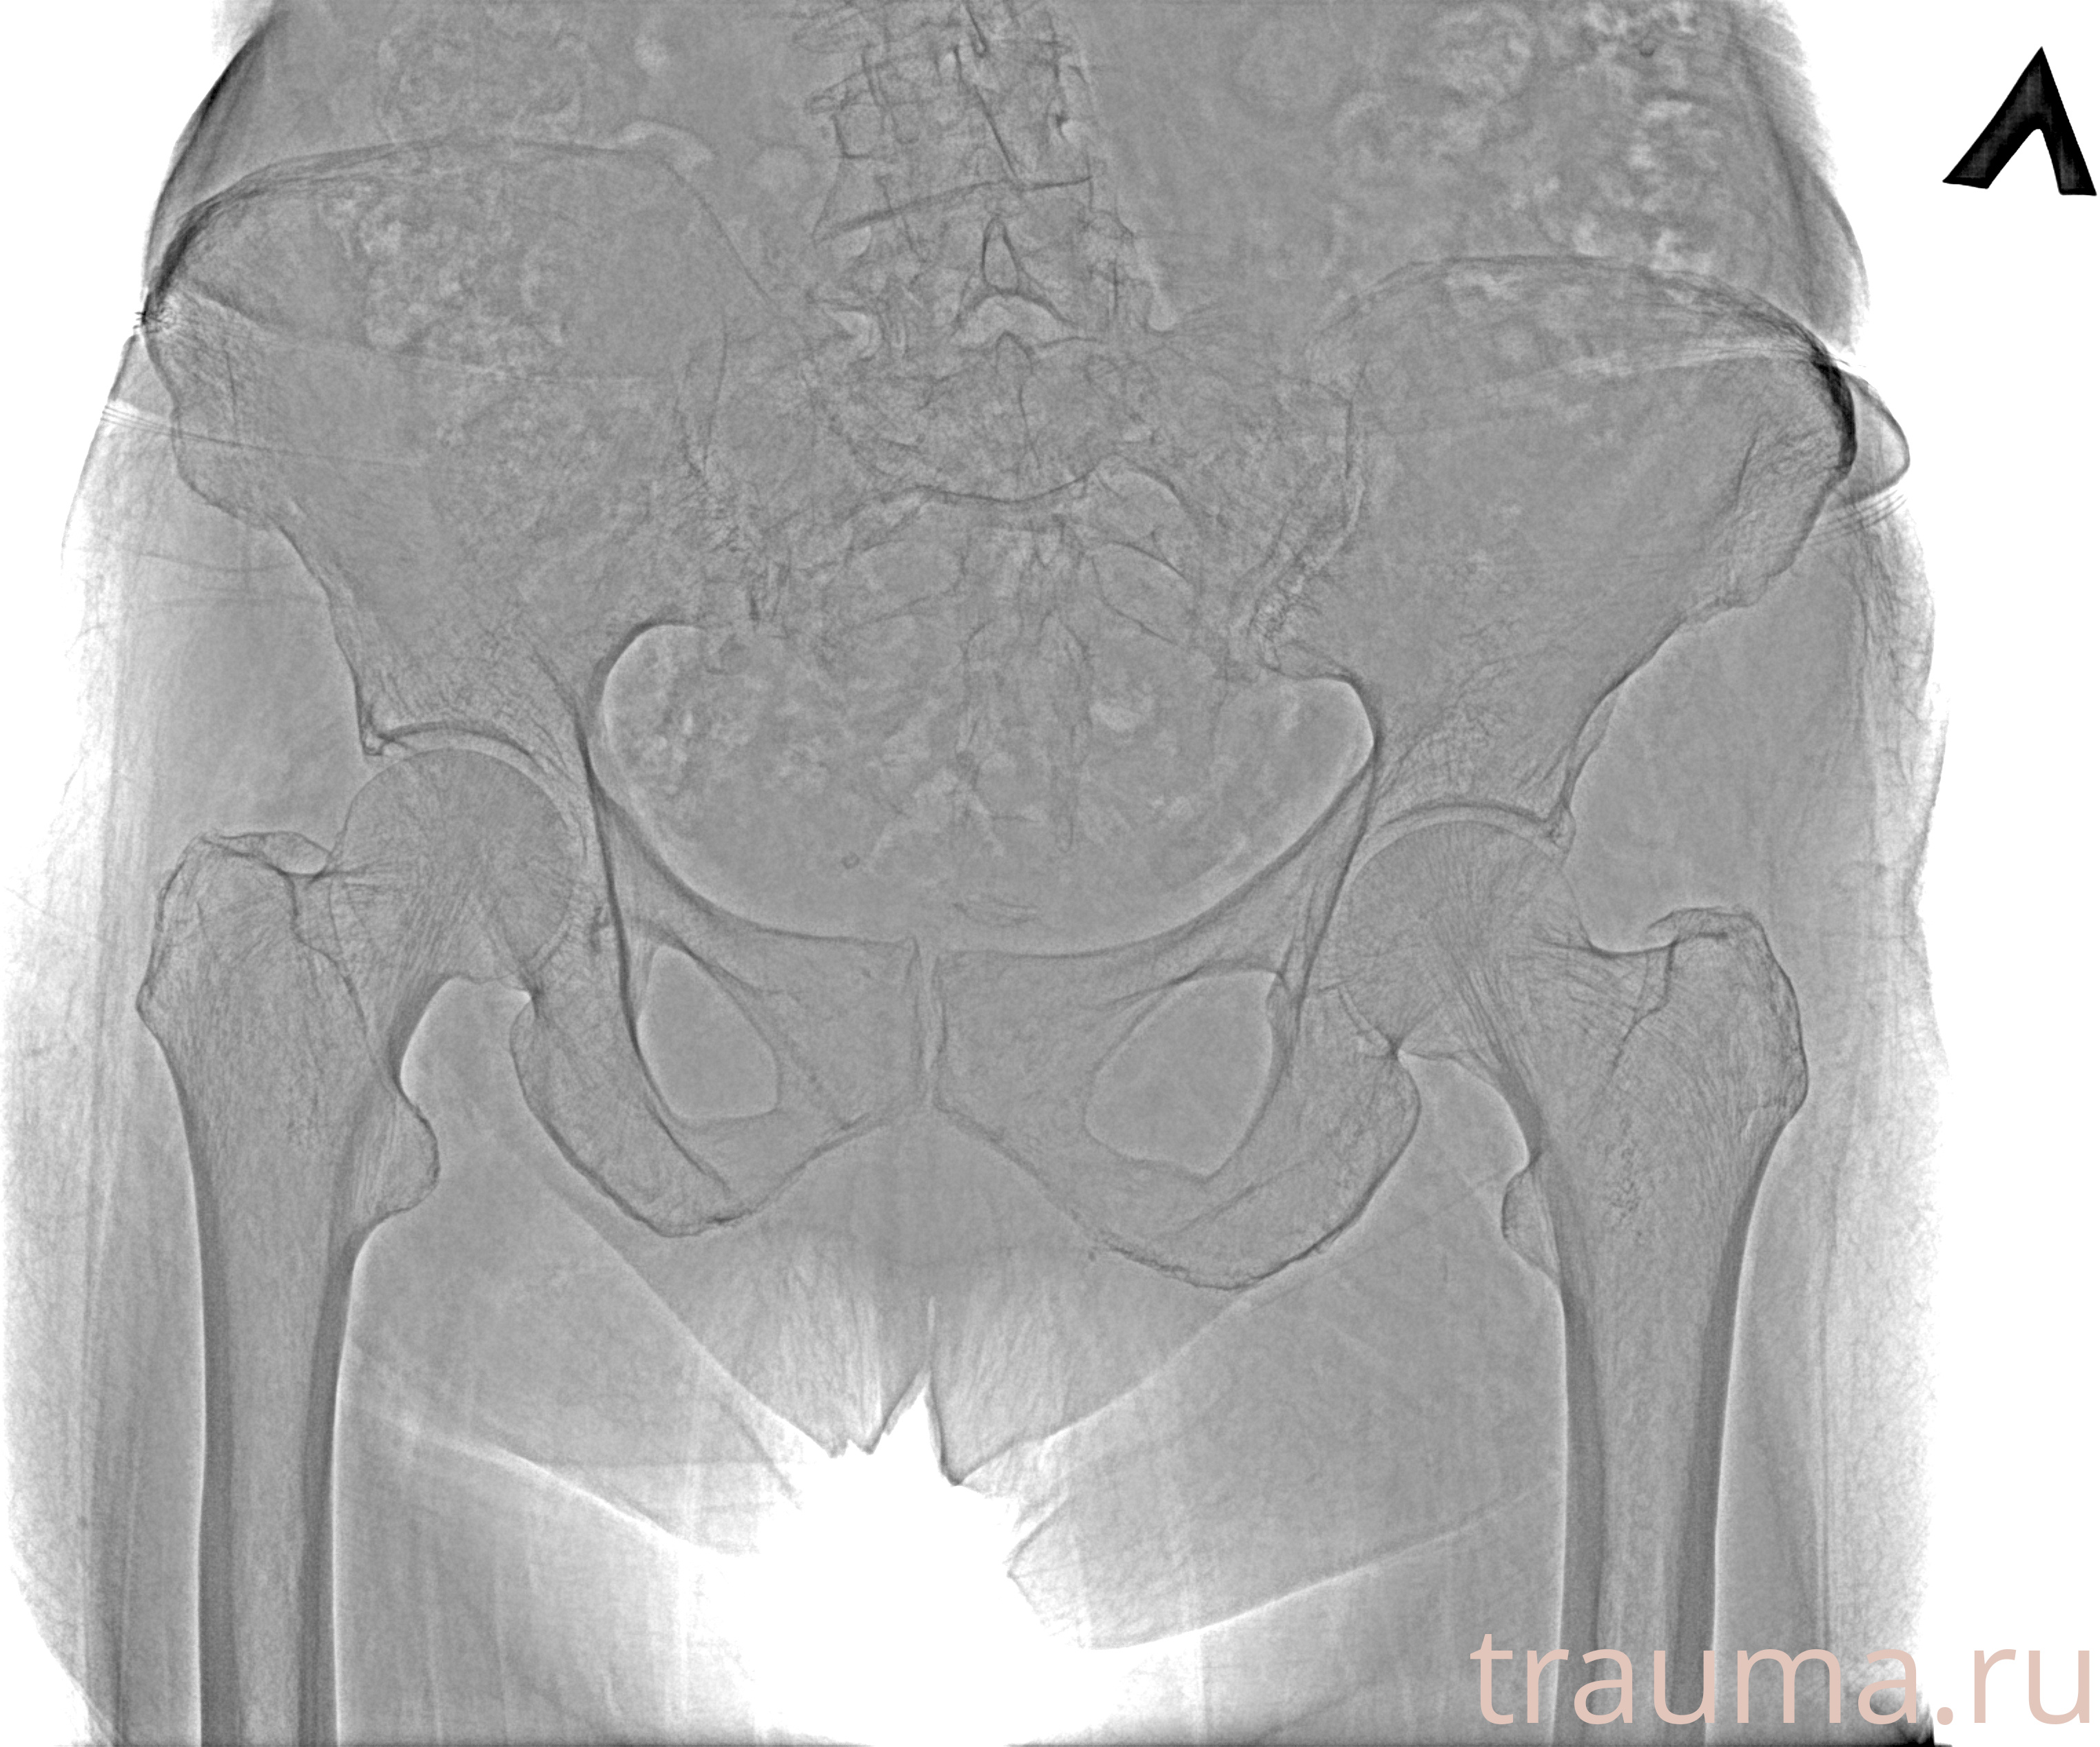

Первая помощь при переломе шейки бедра

Рентген на дому: по вашему адресу приезжает врач-рентгенолог, травматолог-ортопед с мобильным рентгеновским аппаратом, проводит диагностику травмы или заболевания, делает необходимые рентгенограммы, дает рекомендации по дальнейшему лечению. Получить качественные снимки в домашних условиях возможно благодаря уникальной методике, разработанной МосРентген Центром для института  Склифосовского